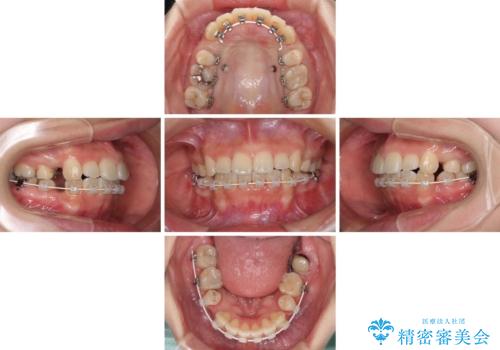

目立たない装置を希望されたので、上顎が裏側装置のハーフリンガルを選択し、上下左右の小臼歯(計4歯)を抜歯して矯正治療を行うこととしました。

デコボコの解消までは非常にスムーズでしたが、咬合力が強いためか、スペースを閉じるまでに長い期間を要しました。

矯正治療途中にインプラント埋入と仮歯の装着を行ったことで、しっかりとした奥歯の咬み合わせで終了させることができました。